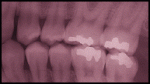

Cavities in teeth are normally drilled clean and then filled with an artificial material. This procedure could become obsolete if a new hormone treatment proves successful:

The gel or thin film contains a peptide known as MSH, or melanocyte-stimulating hormone. Previous experiments, reported in the Proceedings of the National Academy of Sciences, showed that MSH encourages bone regeneration.

Bone and teeth are fairly similar, so the French scientists reasoned that if the MSH were applied to teeth, it should help healing as well.

To test their theory, the French scientists applied either a film or gel, both of which contained MSH, to cavity-filled mice teeth. After about one month, the cavities had disappeared, said Benkirane-Jessel.

Link via Popular Science | Image: NIH